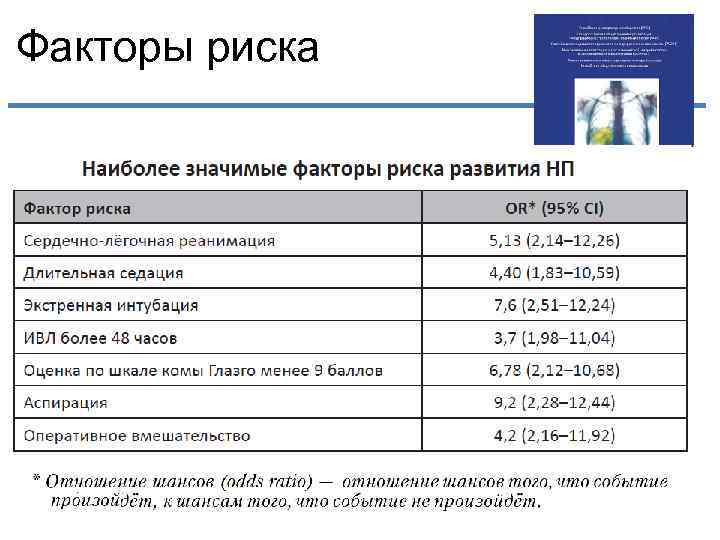

Факторы риска

Факторы риска